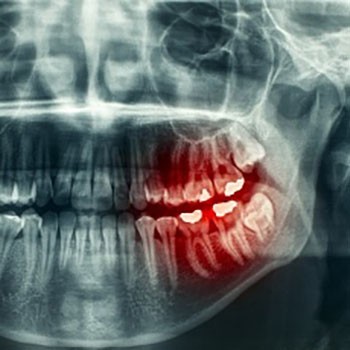

Enzyme Therapy Helps Rebuild Teeth